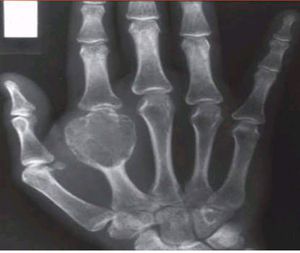

Giant cell tumor

Osteoclastoma